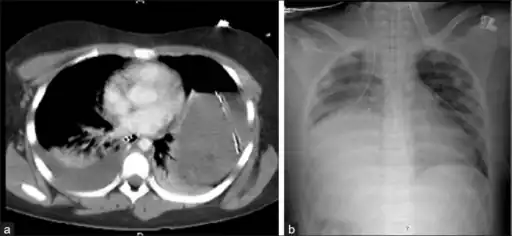

Bilateral blunt diaphragmatic rupture a) confirmation of intrathoracic herniation indicates left hemidiaphragmatic rupture b) post operative image shows elevation of right hemidiaphragm adding suspicion of right diaphragmatic rupture

Axial lower chest CT scan showing bowel herniation due to left diaphragmatic rupture